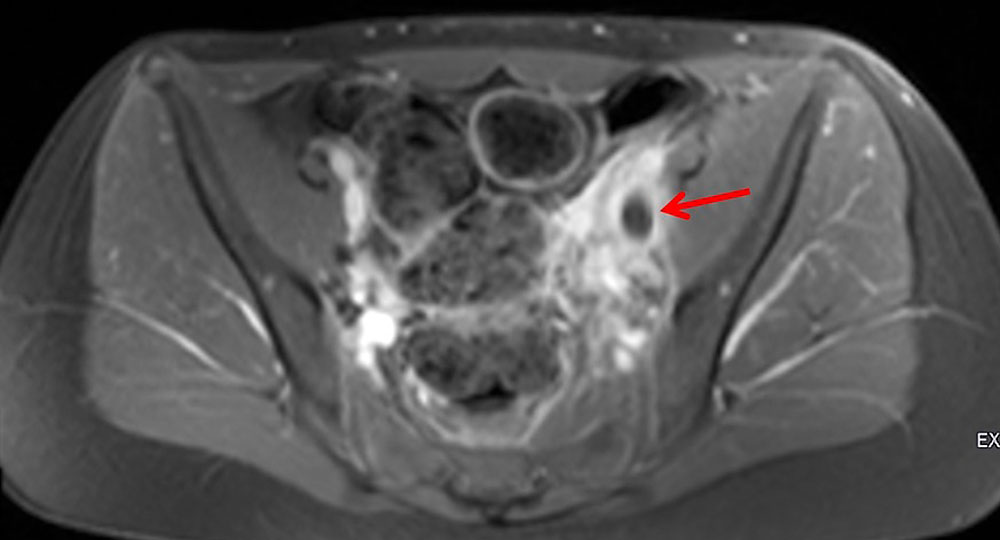

In the case of thrombosis of the central iliac veins, it may be difficult to detect thrombosis by transabdominal sonography because of overlaying structures such as bowel. Phlebography may also produce a false negative in this case. Cross-sectional computed tomography or magnetic resonance imaging may be helpful in such cases if a therapeutic consequence can be derived from it. A good alternative, especially in the area of the proximal common iliac veins, e.g., in May-Thurner syndrome, is intravascular ultrasound, which involves inserting a catheter with an integrated ultrasound probe directly into the vein.